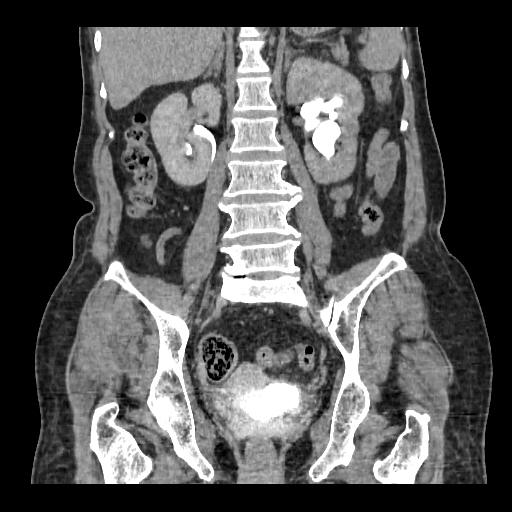

A 50 years old woman with suffering from left sided PUJ obstruction